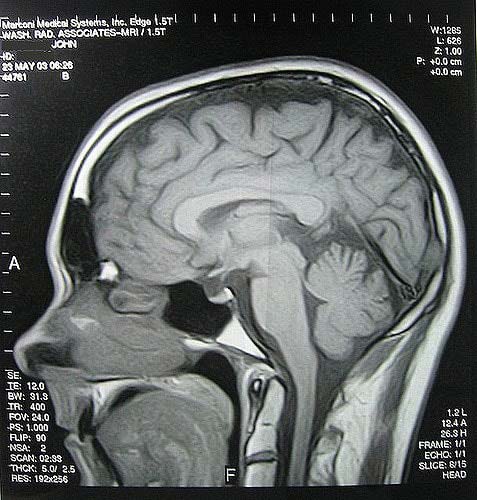

- МРТ. Выявляет патологии сосудов или наличие опухолей. МРТ всего тела покажет наличие нарушений в вашем организме, связанных с сосудами и нервной системой.

Это означает, что в большинстве случаев МРТ помогает поставить правильный диагноз;

Хроническая боль может продолжаться до 180 дней. В таких случаях, почему болит голова каждый день, должен помочь выяснить врач. Он составит подробный анамнез, назначит анализы, в том числе и МРТ.

- МРТ головного мозга;